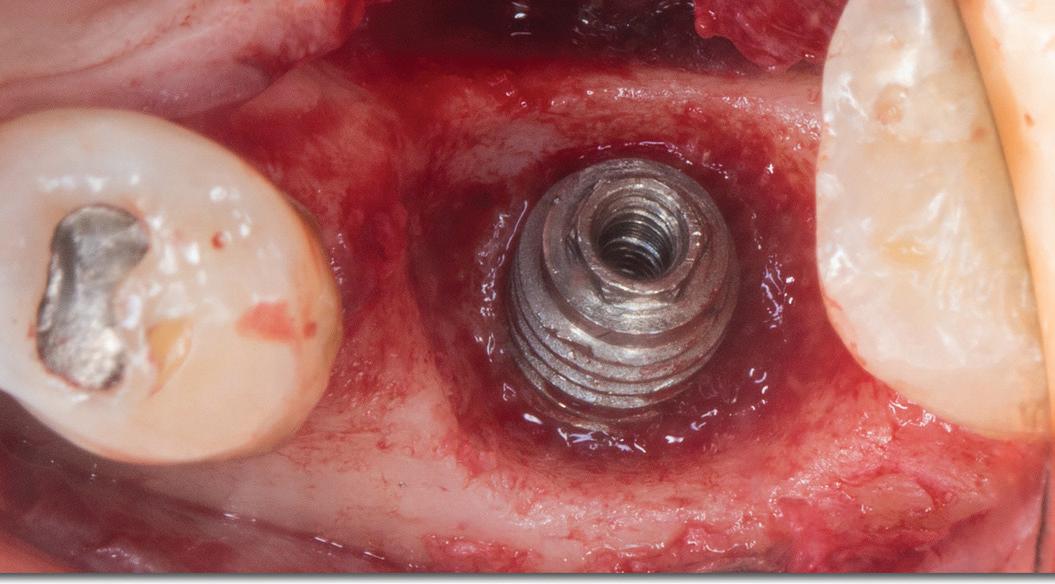

72 Implants

Surgical treatment of peri-implantitis via multiple decontamination procedures and a regenerative protocol: a case report with 6-year follow-up Ísis de Fátima Balderrama

Nicolas Nicchio

Elcio Marcantonio-Junior

Guilherme José Pimentel Lopes de Oliveira

Ana Carolina Monachini-Marcantonio